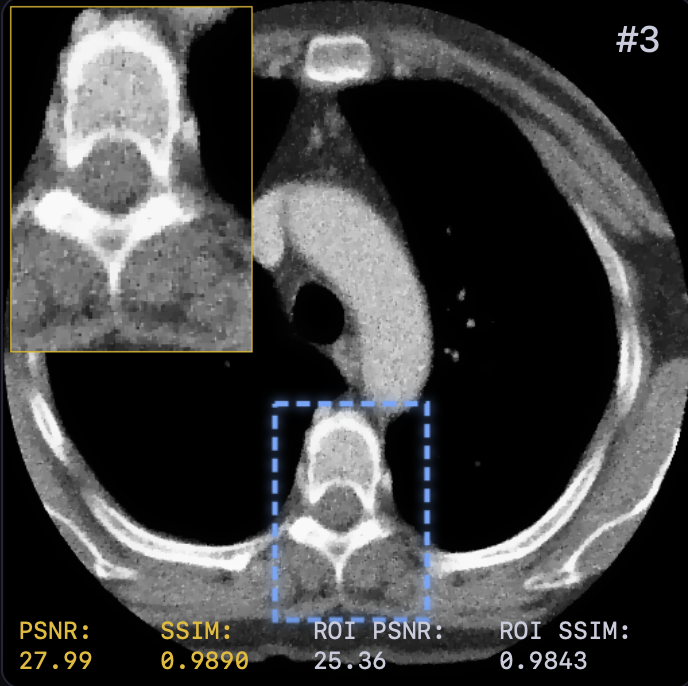

Table I presents the quantitative comparison. LTV achieves the best overall performance, surpassing FBP+U-Net [5] by approximately dB PSNR. Notably, learning the solver dynamics yields a consistent gain ( dB PSNR) over the fixed-solver baseline (29.42 vs. 30.15 dB). This confirms that end-to-end optimization of step sizes and relaxation provides modeling capacity beyond spatial adaptivity alone.

Qualitative results (Fig. 2) demonstrate that LTV preserves fine structures (e.g., vessel continuity) while avoiding the over-smoothing of classical TV and the anatomical inconsistencies of FBP+U-Net. This is corroborated by the error maps in Fig. 3, where LTV exhibits smaller and more spatially uniform residuals, indicating a balanced trade-off between noise suppression and detail preservation.